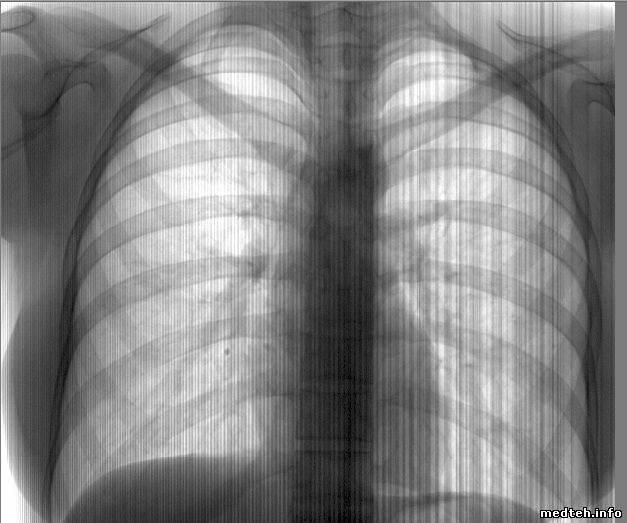

Аппарат Проскан-2000.

На снимках появились горизонтальные полосы. Может кто сталкивался?

8205200.jpg (86.5 Kb) · 2394374.jpg (85.0 Kb)

Интересуют именно горизонтальные полосы. Наклонные - это мерцание, которое улавливает фотоаппарат, на глаз их нет.

Это дефекты линейного детектора. Обращался с такой проблемой к проскановцам, отослали к производителю детекторов. А те отослали на Проскан.

Похоже на битые каналы, но они появляютя по одному, а не пачкой. Я бы посмотрел питание детектора, похоже просажено.